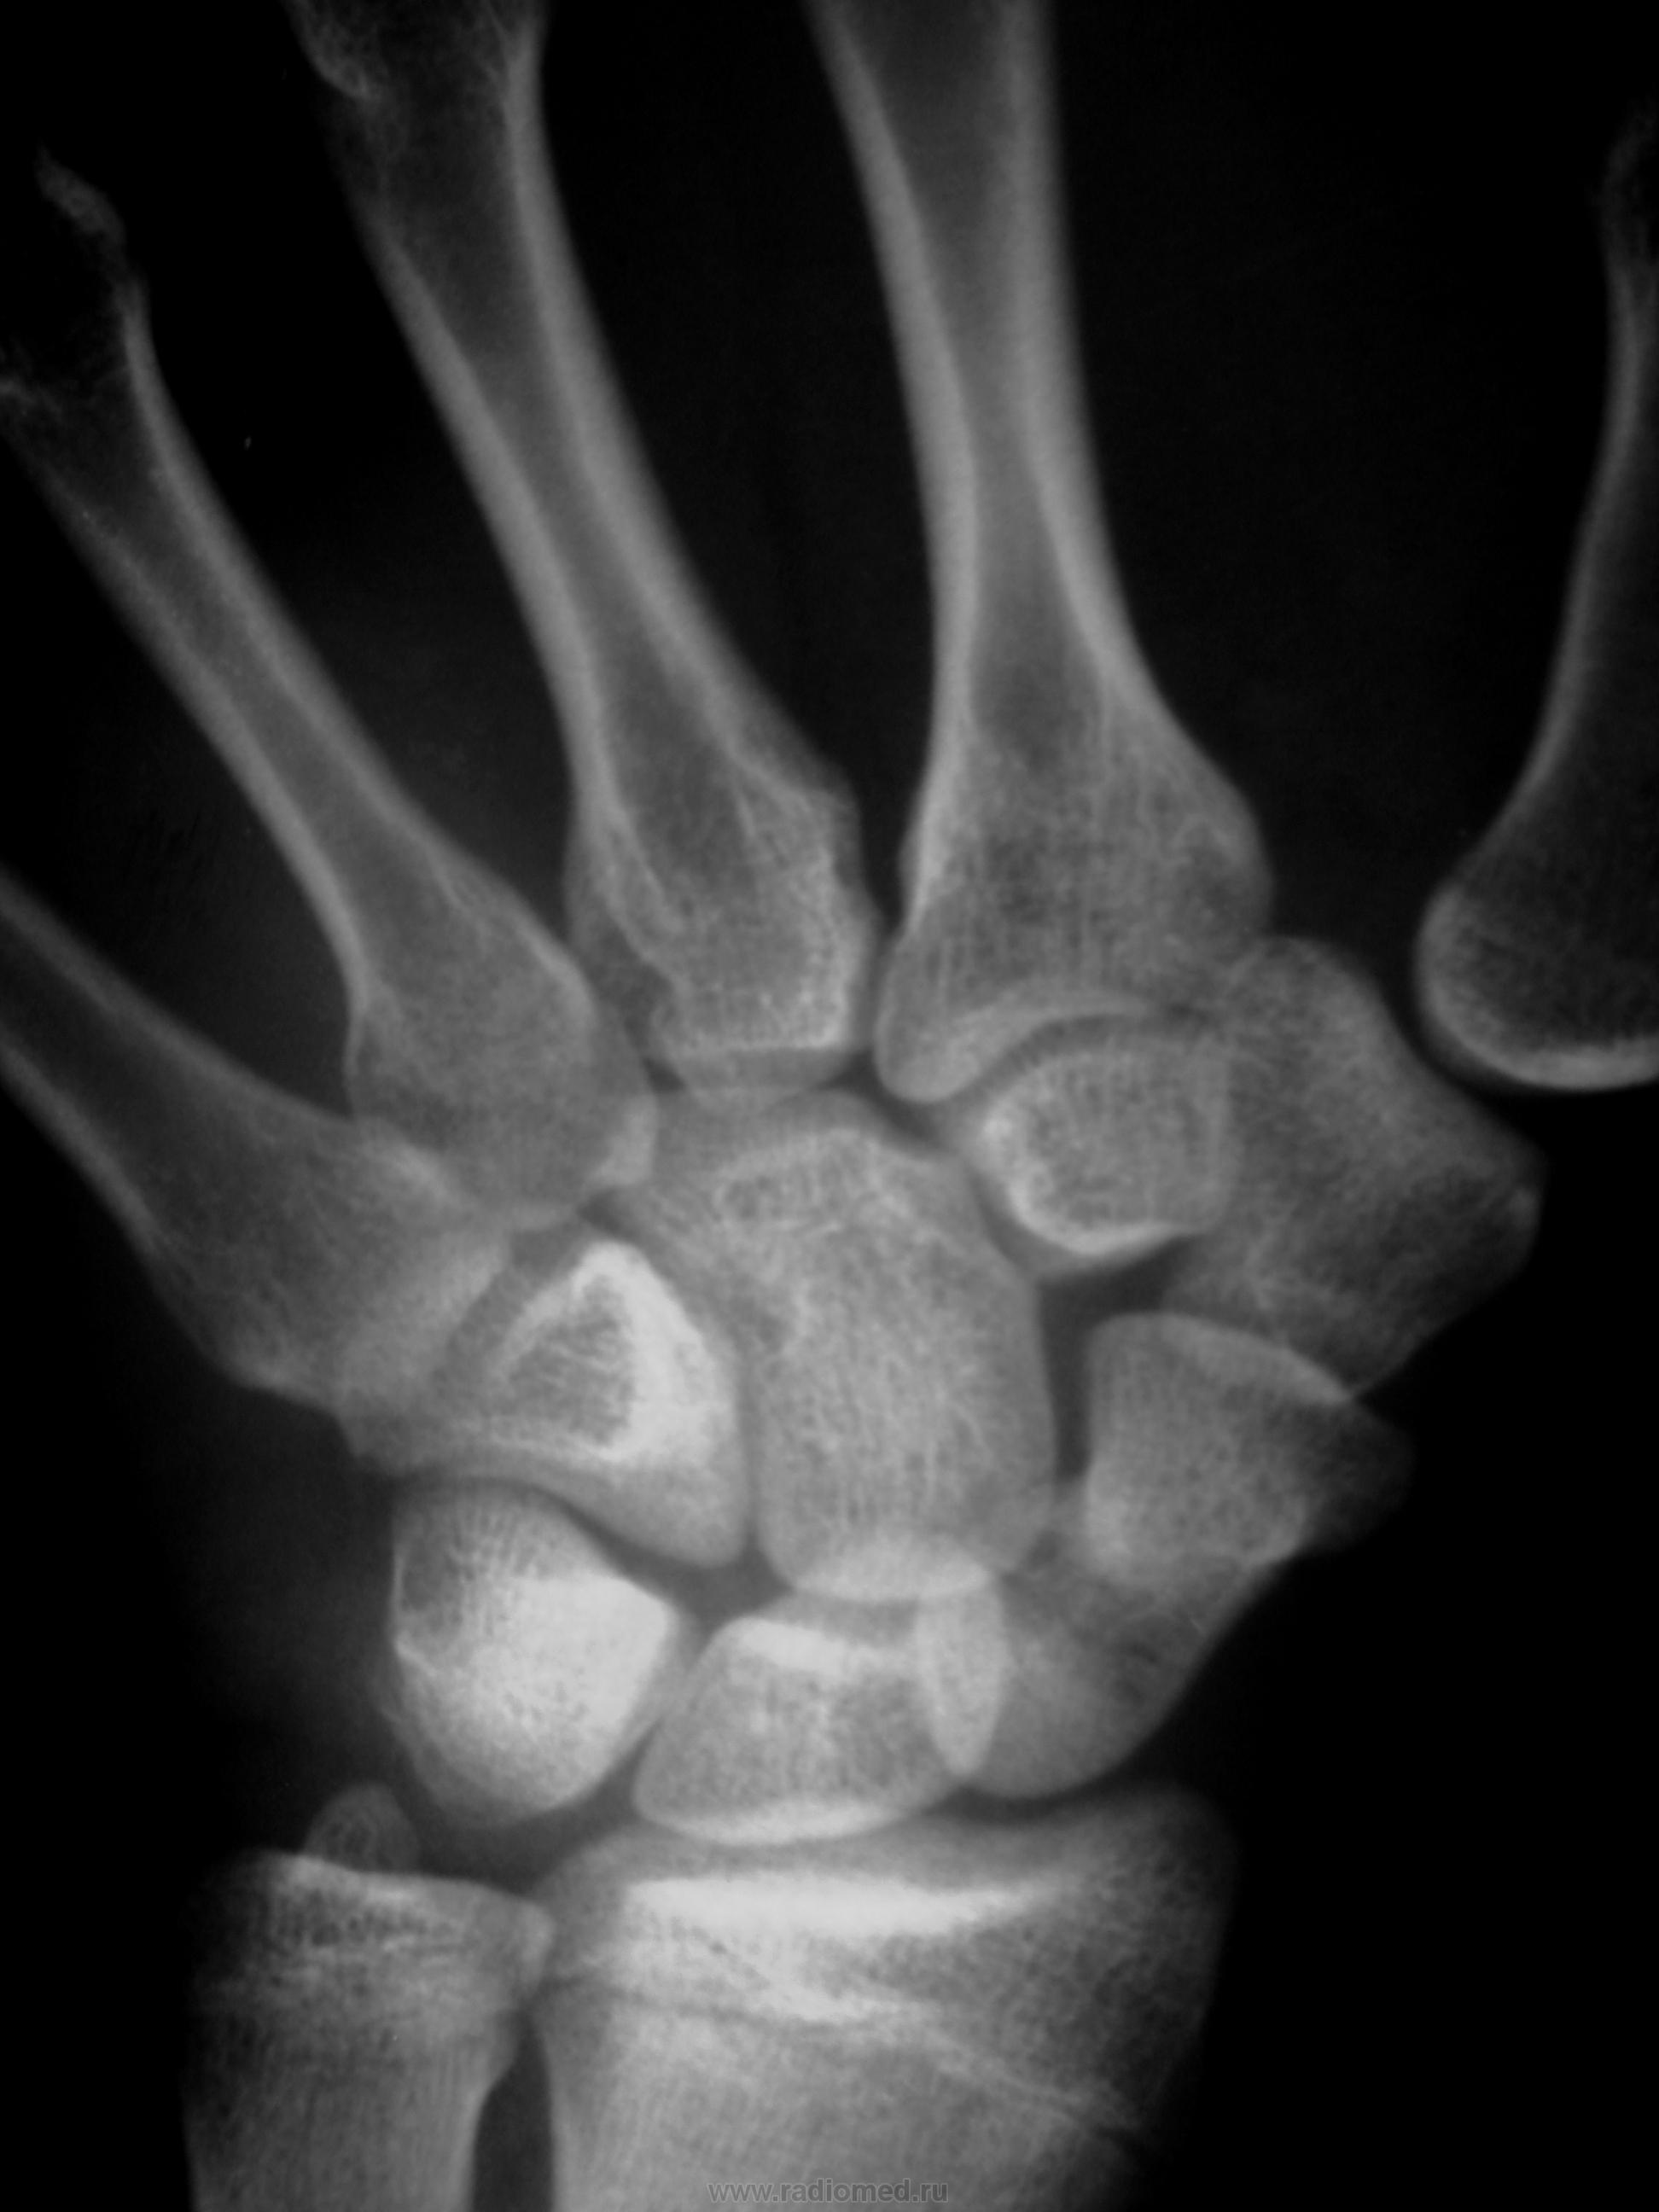

Травма в октябре 2009,сейчас появились боль, припухлость в обл. ладьевидной кости. Какие будут мнения, уважаемые коллеги?

Значит в октябре не болело. Это странно. Несросшийся перелом есть. А вот псевдартроз как-то не очень... Здесь нужна проекция для ладьевидной кости, без наслоений других.

В  октябре само сабой болело,перелом был диагносцирован,ходил в гипсе, но через месяц сняли и носили ортез. Не болело до настоящего времени.

В наших условиях - знатоки говорят о необходимости операции чуть ли не в первые 2 часа после перелома, переломы ладьи никогда не срастаются...